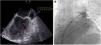

The cardiac computed tomography provided information for the anatomical mapping of the four pulmonary veins (PV) and excluded intracardiac thrombus. Immediate preprocedural transesophageal echocardiography found low velocity flow within the LAA, and LAA smoke, without thrombus formation (Figure 1A). DC cardioversion was attempted in the laboratory before PVI, without conversion to sinus rhythm (SR). PVI was then performed using a cryoballoon catheter (Arctic Front Advance; Medtronic) and a dedicated inner-lumen mapping catheter (Achieve Advance 2; Medtronic). During the procedure, an activated clotting time level around >300 s was reached following heparin administration. Elimination of all PV potentials was obtained (240 s per vein; ranging from -43°C (right inferior PV) to -52°C (left superior PV). Due to three failed DC cardioversion attempts after PVI, and evidence of a short cycle length on the LAA electrograms (180 ms), LAA was targeted and electrical isolation obtained with a 180s cryo-application (time-to-isolation: 90 seconds; -48°C) (Figure 1B and Figure 2). After LAA isolation, 100 j successfully converted PersAF into SR. PVI and LAA isolation were confirmed by entrance-and exit-block. The procedure time was 75 minutes, with 13 minutes (434 μGy) of fluoroscopy.

A. Transesophageal echocardiography imaging of the left atrial appendage in atrial fibrillation before ablation. Blood flow velocities (on the right top) showed low peak emptying velocities (<40 cm/s). B. Fluoroscopic image showing contrast injection with complete occlusion of the left atrial appendage (white arrows) by the inflated cryoballoon. Advance Achieve 2 circular catheter is placed inside the left atrial appendage (left anterior oblique view).